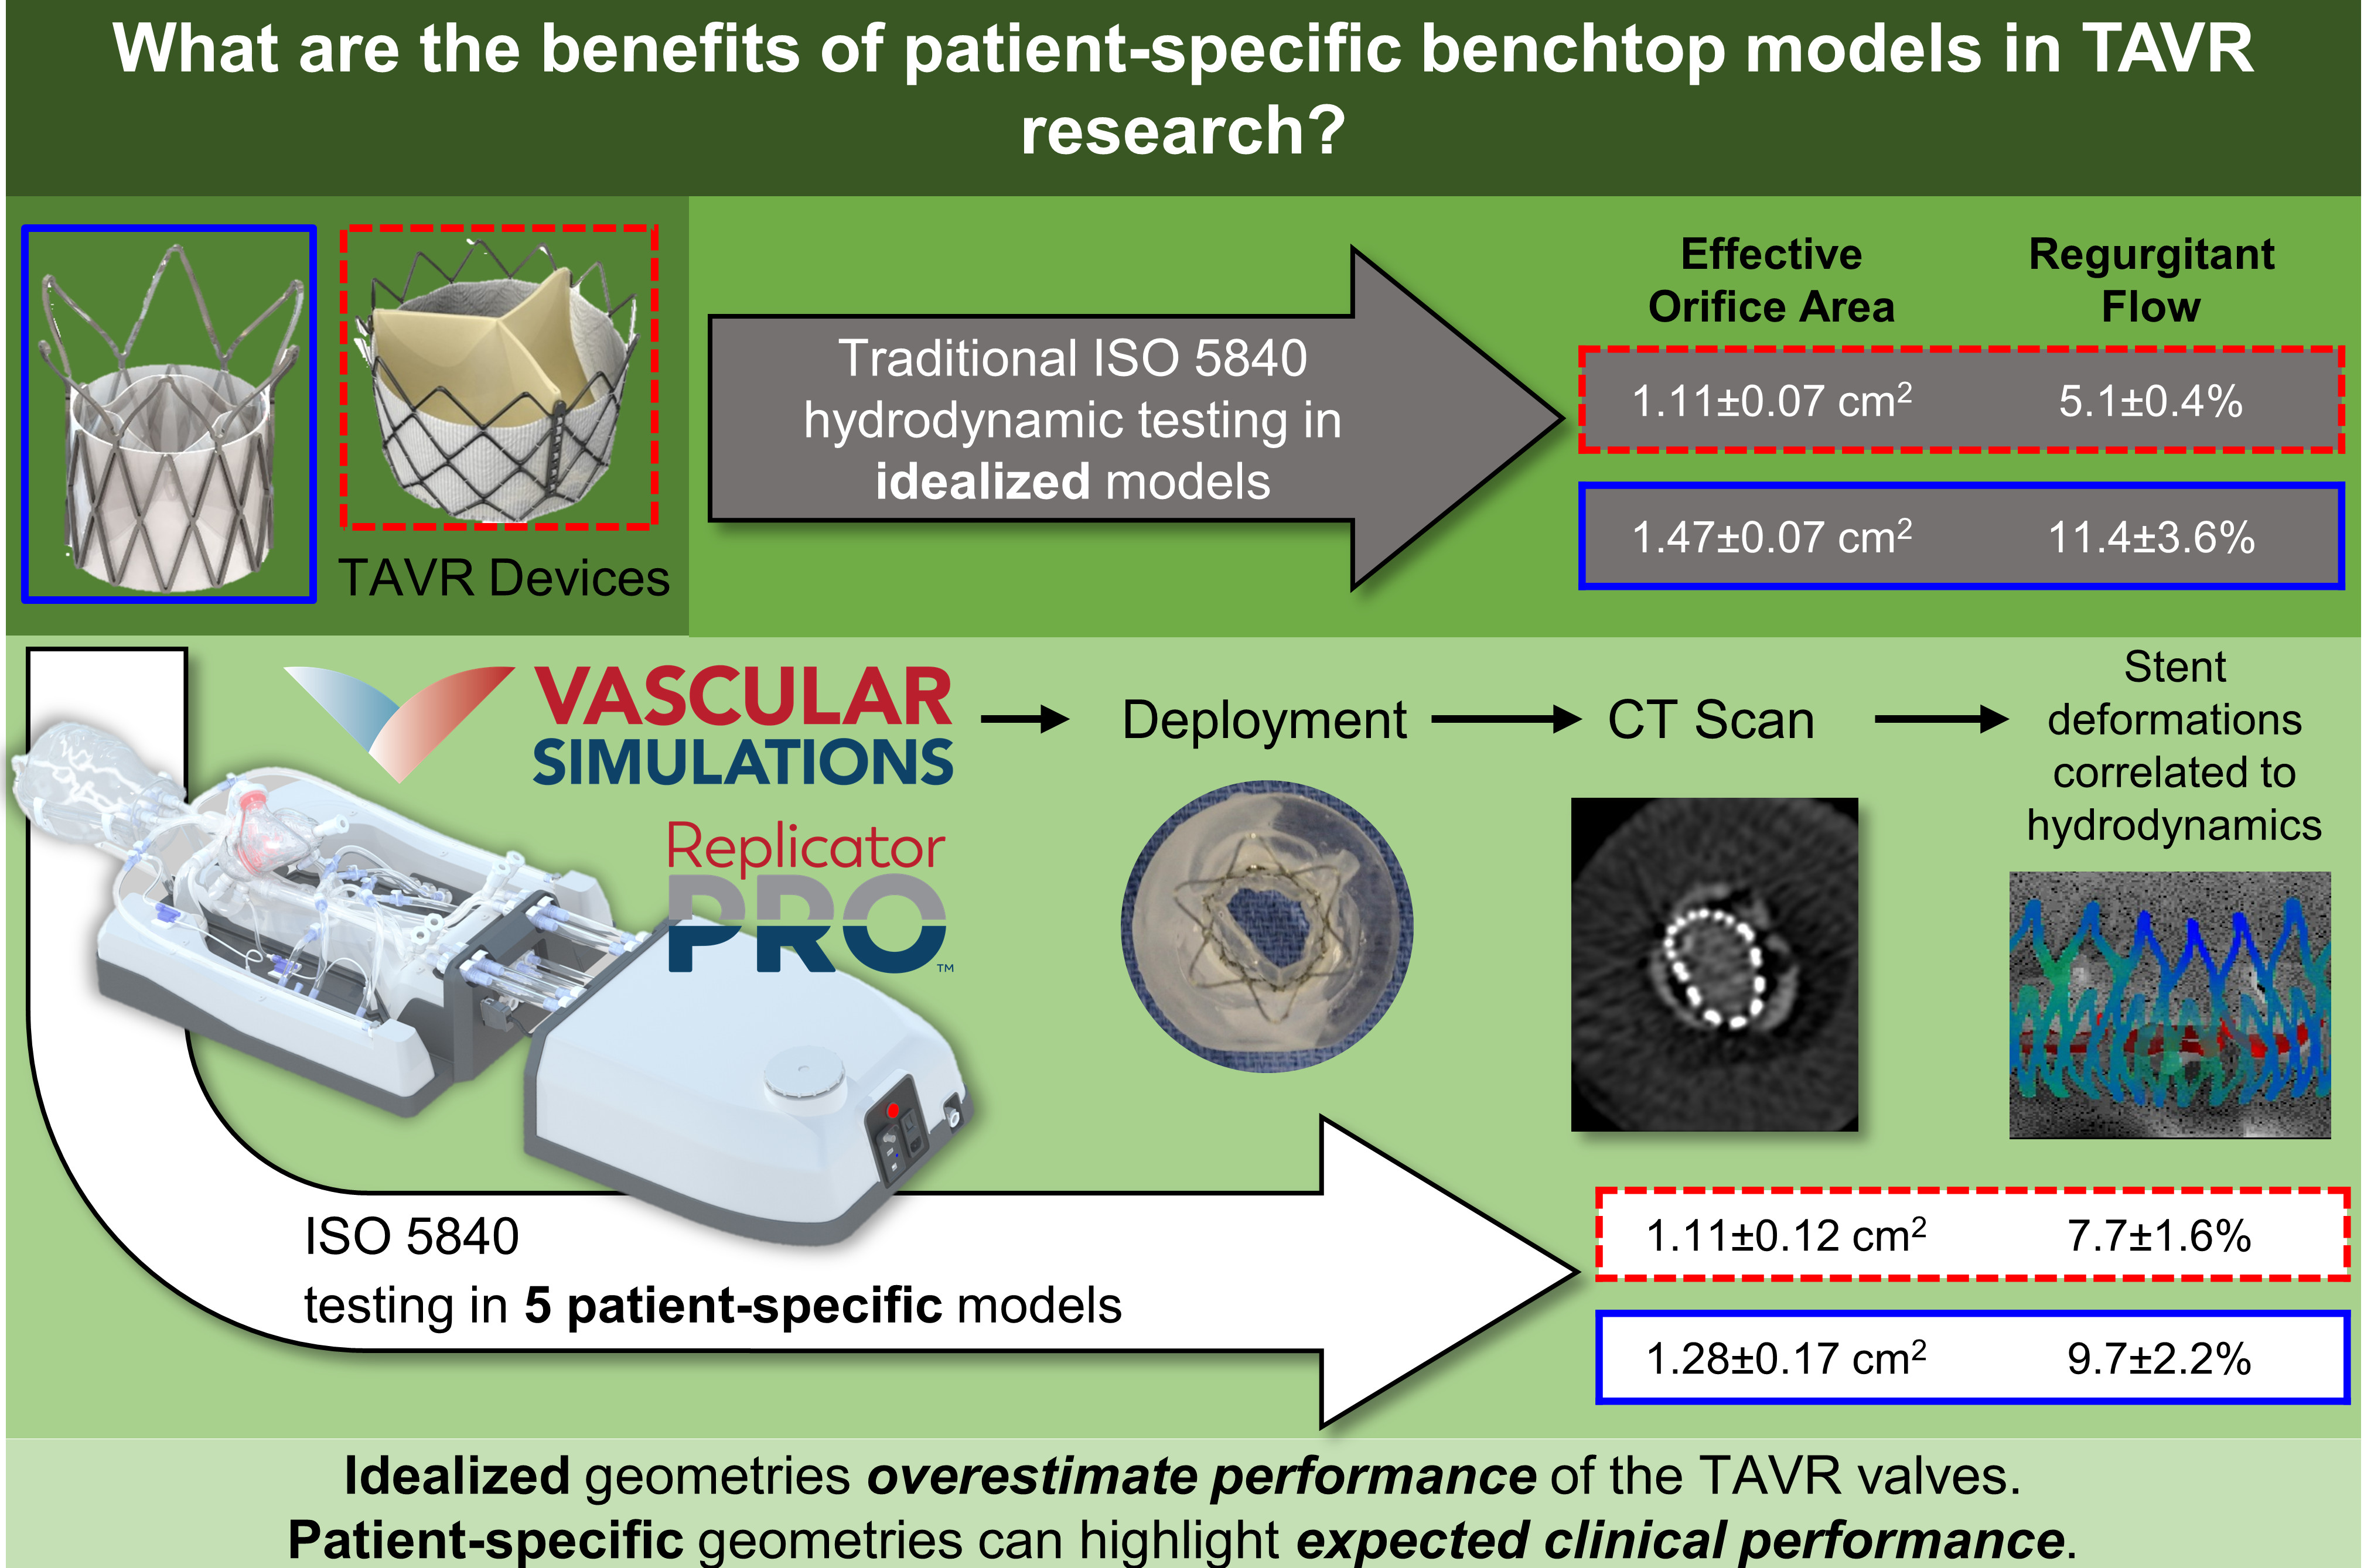

Patient-specific In-Vitro Models for TAVR Performance Evaluation

Traditionally, TAVR valves are benchmarked and evaluated with the ISO 5840 standard,

which was originally designed for surgical valve testing, and negates key anatomical

features of aortic stenosis patients. The interaction between the TAVR stent frame

and the unique/ irregular calcific masses inside the patient leaflets define the deployed

shape and therefore the functionallity of the valve.

The goal of this research was to develop a patient-specific replica of calcific aortic

valve disease(CAVD) to emulate the expected clincial performance of the TAVR devices.

In collaboration with Vascular Simulations, we developed such a model to interface with the advanced simulation system called

the Replicator Pro, which allows us to study various patient anatomies inside the

cath-lab as if it was a patient on the table. We can rapidly deploy, measure and image

the valves for clinical evaluations as well as develop more adavanced imaging techniques

such as an intra-procedural CT for measure the coaption of the stent to the replica

lumen.

Two different TAVR devices, one self-expandable polymeric and one balloon-expandable tissue valve, were evaluated according to the ISO 5840 guidelines but in five different patient models. The patient-specfic results were compared to the idealized geometry simulator commonly used in ISO 5840 testing, and we showed that the current standards can dramitically overestimate the performance of the valves.